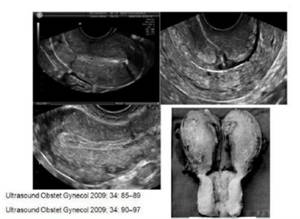

(图:剖宫产子宫瘢痕缺陷)

(图:疤痕妊娠)